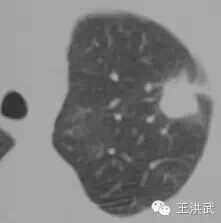

冷冻前肺内3cm(直径)肿块

冷冻10个月后,肺内肿块基本消失